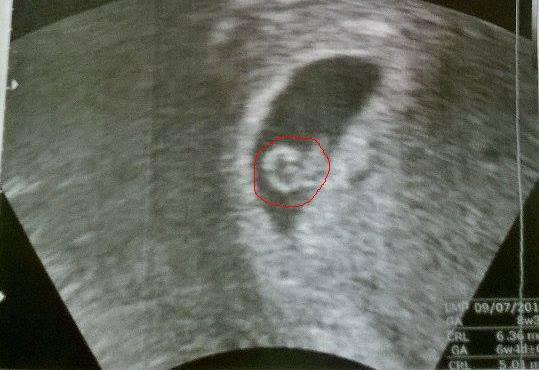

@xyrina dnešní ultrazvuk a srdíčko bilo 🙂

@nadla Parádní fotka 🙂 a vůbec nevadí, že je černobílá, co? 😀. U mě se dnes hlásí MS.

@xyrina 😃 nevadí ..bože já jsem dojatá ještě teď. Jsem 8tt a 3dny. Za chvíli začínám 3měsíc ty brďo. ..... Ajaj, ale aspoň buď ráda, že nějakou máš. Držim Ti furt palce a ja věřim, že se Ti to podaří. 😘